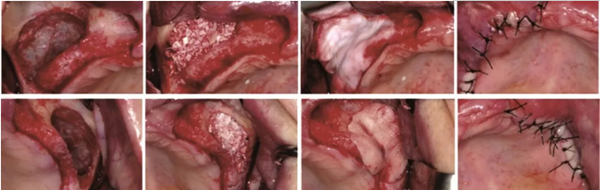

1、CGF/PRF作為屏障膜使用

在引導骨再生術(shù)中,需要使用可吸收或不可吸收的屏障膜,為骨組織的再生提供不受干擾的空間。如果使用CGF/PRF作為屏障膜,其相對目前臨床使用的可吸收生物膜是否具有優(yōu)勢?Gassling等進行了一項臨床研究[4],研究納入了6例需要進行雙側(cè)上頜竇外提升的患者,在完成植入骨替代材料后,一側(cè)使用PRF壓制而成的屏障膜覆蓋開窗處,而另一側(cè)則使用目前臨床廣泛使用的Bio-Gide生物膜覆蓋,如圖1示,以對比兩者的差異。作者發(fā)現(xiàn),術(shù)后患者兩側(cè)水腫、疼痛及初期創(chuàng)口愈合情況無明顯差異,術(shù)后5個月行種植體植入術(shù)時,作者同時取出部分骨組織行組織學評估,發(fā)現(xiàn)兩組在新生骨的比例和骨替代材料的剩余比例上均無差異。

學者研究發(fā)現(xiàn),單獨使用CGF/PRF作為屏障膜,因為其降解速度較快,無法達到理想的屏障效果。當聯(lián)合生物膠原膜使用時,未見明顯的促進成骨效果,同時增加了手術(shù)費用和手術(shù)難度。亦有學者表示CGF/PRF作為膜使用,聯(lián)合生物膠原膜應用于GBR植骨術(shù)中時,可以促進局部軟組織的愈合,降低感染的幾率。